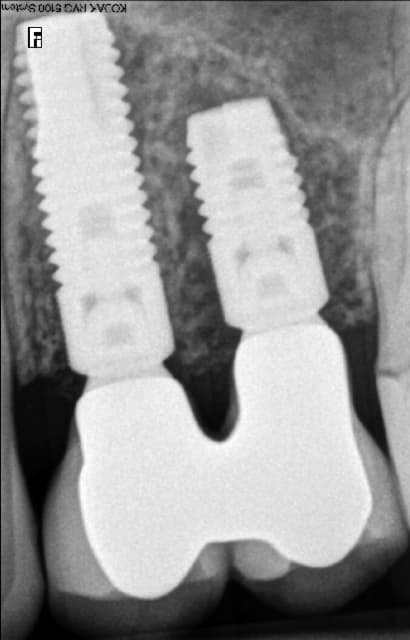

Par contre si je peux me permettre, tu devrais y aller mollo sur les filtres pour tes radios, sur le cliché présenté l'os paraît un peu bizarre, on pourrait presque croire que les implants ne sont pas ostéointégrés.

Le Choixpeau magique écrivait:

------------------------------

> Superbe résultat !

>

> Par contre si je peux me permettre, tu devrais y aller mollo sur les filtres

> pour tes radios, sur le cliché présenté l'os paraît un peu bizarre, on pourrait

> presque croire que les implants ne sont pas ostéointégrés.

ils bougent juste un peu ;)